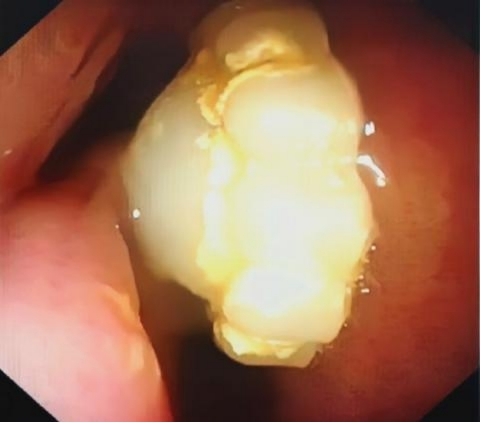

4月12日,湖南省儿童医院耳鼻咽喉头颈外科门诊接诊了一位家住长沙芙蓉区的7岁女孩然然。爸爸在1年前发现孩子有轻微鼻塞,睡觉打鼾,张口呼吸,一直未引起重视,直到近期症状越来越重,以为孩子是腺样体肥大才带孩子来到我院就诊。接诊医生通过仔细检查,感觉孩子鼻腔内似有异物,反复询问孩子自己是否往鼻腔内塞过东西,然然否认了,家长也说没有看到她塞过东西。医生给她完善了电子鼻咽喉镜检查,结果显示右侧鼻腔确有一异物。接诊医师通过使用耳鼻喉科专科器械,顺利从然然的鼻腔内取出一颗粉白色圆形塑料珍珠,直径大约0.5cm。

取出异物后,医师再次询问然然,“这个珠子是怎么进到鼻子里的呀?”,然然这才战战兢兢地道出原委。原来,早在一年前读幼儿园时,然然和小伙伴玩耍,对鼻子两个“洞洞”充满了好奇。在探索欲的驱使下,她将手中的塑料珍珠塞进了鼻孔。没想到塞进去后就拿不出来了,因为害怕被责骂,她不敢告诉老师和父母,这颗“珍珠”就这样在她的鼻子里整整“潜伏”了一年。